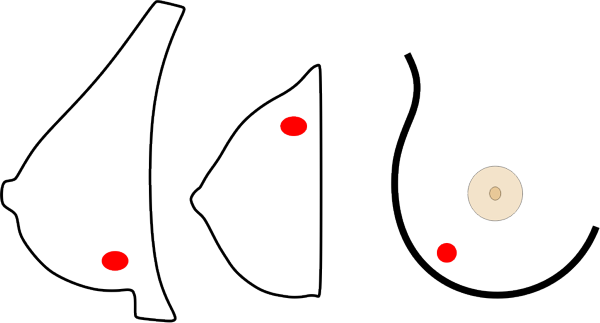

Die Brust ist ein dreidimensionales Organ, die Aufnahmen sind hingegen flach. Um die sichtbaren Strukturen räumlich richtig einordnen zu können, sind daher zwei Aufnahmen in verschiedenen Ebenen notwendig.